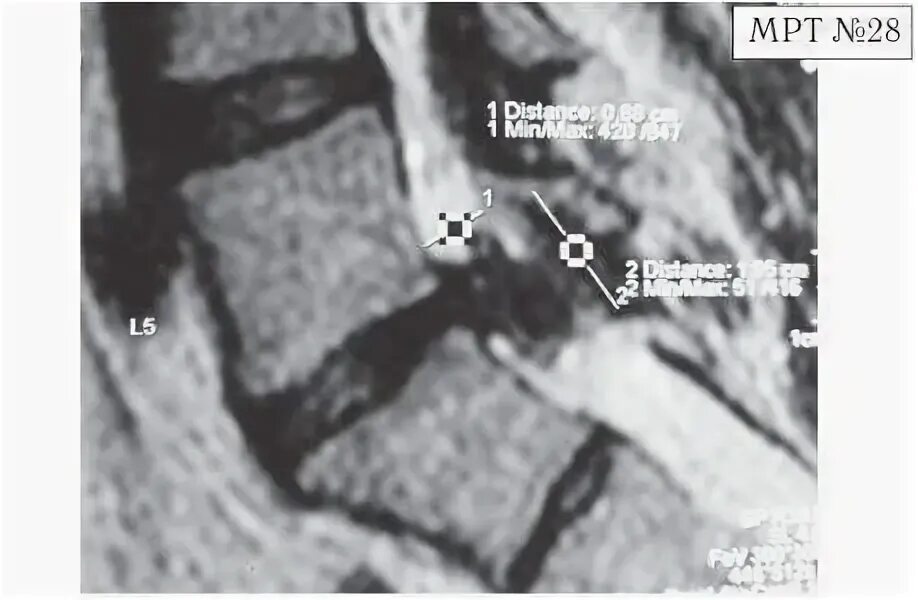

Задняя центральная экструзия диска l5-s1. Резорбция грыжи межпозвонкового диска. Экструзия межпозвоночного диска l5-s1 с каудальной миграцией. Грыжа с миграцией. Грыжа с миграцией.

Каудальная миграция грыжи l5 s1. Секвестрированная грыжа l5-s1 мрт. Каудальная миграция грыжи что это. Протрузия l3-l4. Резорбция грыжи схематично.